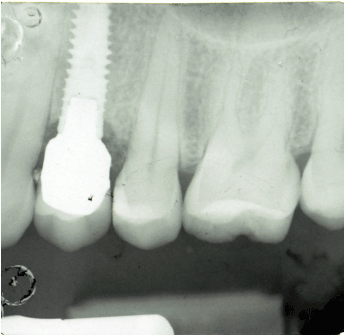

Between January and December 2001, a total of 153 implants had been placed in 134 patients; 68 implants were placed in the maxilla (44%) and 85 implants were placed in the mandible (56%); (Figure 1). 11 patients were lost to follow-up during the period of the study( deceased, transferred, ecc) . 153 Xive S implants were placed for single tooth replacement, with diameters as follows: 3.0 mm (n=11), 3.4 mm (n=87), 3.8 mm (n=14), 4.5 mm (n=40), and 5.5 mm (n=1; (Table 2). Different lengths of the implants were inserted, according to the following distribution: 8 mm (n=3), 9,5 mm (n=210) 11 mm (n=54) 13 mm (n=62), and 15 mm (n=15); (Table 3)( Figure 2). 126 implants of 153 were inserted without any bone regeneration, sinus grafting, or other advanced osseointegration procedures.

Figure 2. Xive S implant inserted in March 2001.